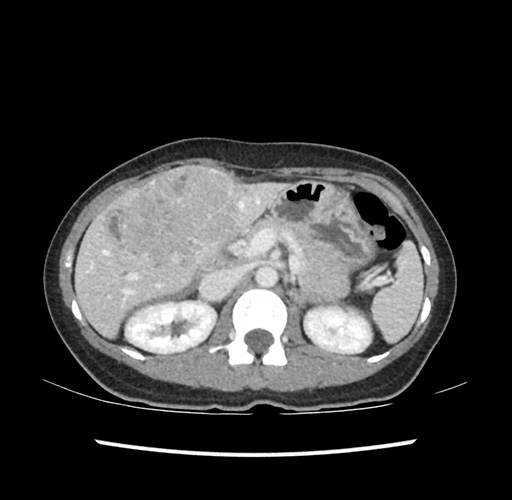

Imaging Analysis

Look through the patient's CT scan to identify any areas of concern for the necessary procedure.

Based on your CT findings, which issue(s) would give reason for "planned slowing down moment(s)" in this case?